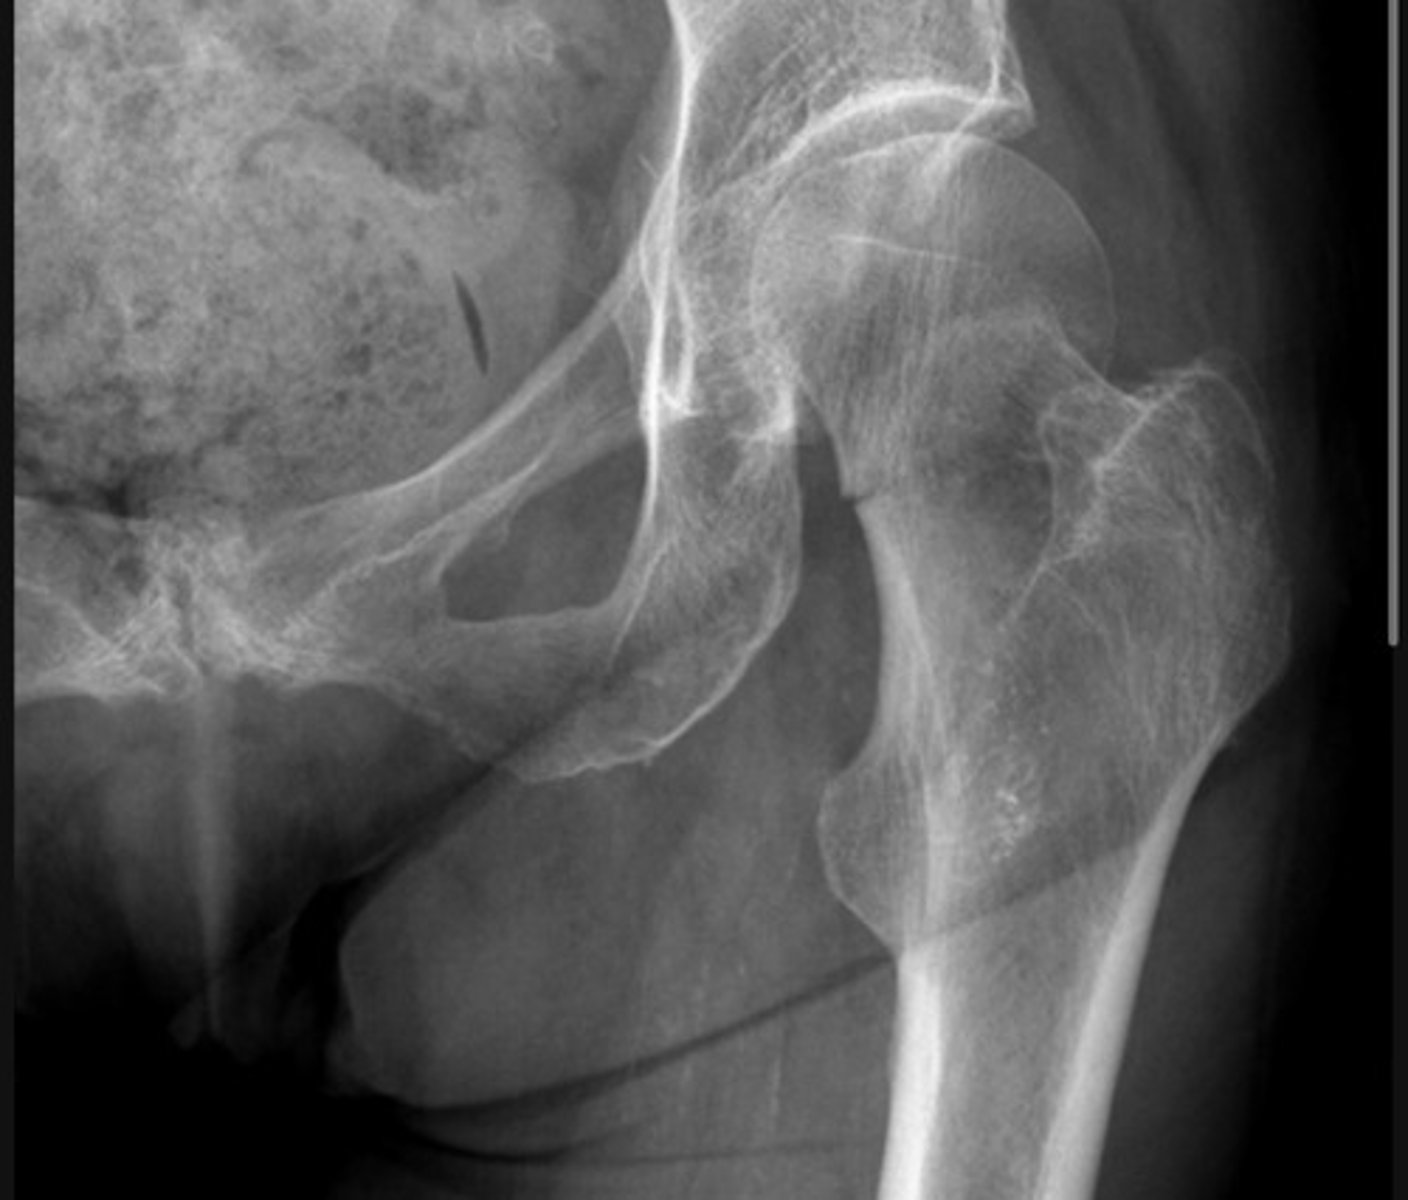

Subcapital fracture with complete displacement

Transcervical fracture with minor displacement

Subtrochanteric fracture

The bone texture is abnormal in this patient with a known malignancy - indicating a pathological fracture

A fracture of the femoral neck is accompanied by avulsion of the greater trochanter